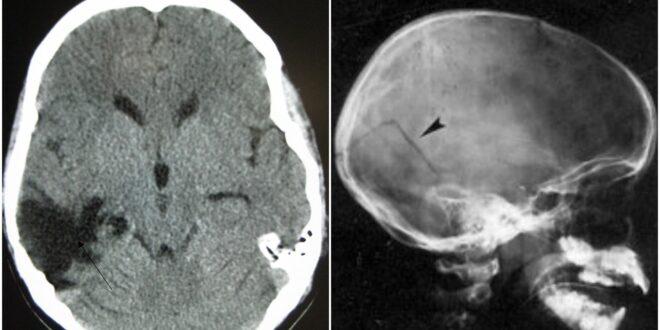

¿Qué es una contusión profunda de cráneo?

En el apartado de lesiones, los textos Medicina Legal y Forense señalan que una contusión es producida por la acción de un cuerpo duro de superficie obtusa o roma.

Dicho cuerpo puede ser un instrumento diseñado específicamente para lesionar o alguno para otro propósito, así como partes del organismo de seres vivos. Como ya se dijo, la particularidad es que el cuerpo o superficie es de forma obtusa.

Las contusiones se manifiestan en el cuerpo en la forma de manchas de color rojo oscuro, debido a la sangre coagulada o extravasada que infiltra los tejidos. Se trata de lesiones muy frecuentes en la práctica médico-legal.

En el caso de las contusiones craneales, dependiendo de la intensidad del impacto, la fuerza puede transmitirse desde el hueso hasta el cerebro.